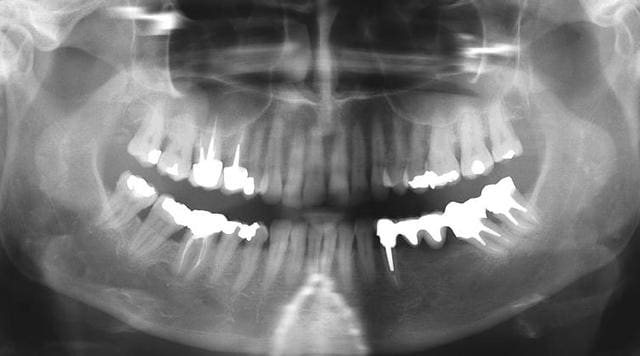

T'aurais des radios?

Image r6habu - Eugenol